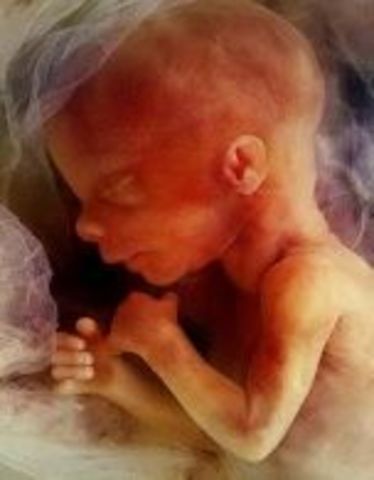

• Week Ten: Embryo is now a Fetus

Week Ten: Embryo is now a Fetus

The developing organism is called a fetus.It is the size of a small strawberry.